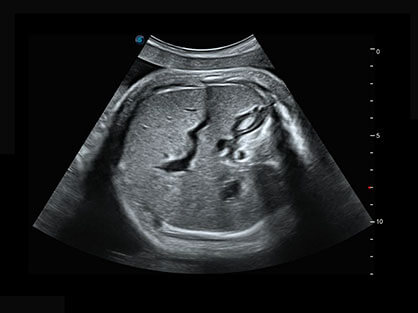

作为P系列家族成员之一,P40 Plus采用狗万官方网站高端超声系统平台——极光,并以时尚秀丽、小巧灵动的外观设计绽放出灵动之韵、科技之美。高端平台的使用保证了P40 Plus优质的基础图像;完备的高级功能可满足您全身应用的基本需求;丰富的探头配置、多样的高级4D成像及分析软件为您日益增多的妇产应用需求提供丰富的诊疗方案。

结合狗万官方网站超宽频带探头技术优势,能够更好地获得高分辨力与高穿透力的平衡,保证图像质量,为临床诊断保驾护航。

微米成像技术提升了对组织斑点噪声信号的抑制能力,并进一步强化边界信息,从而获得清晰图像。